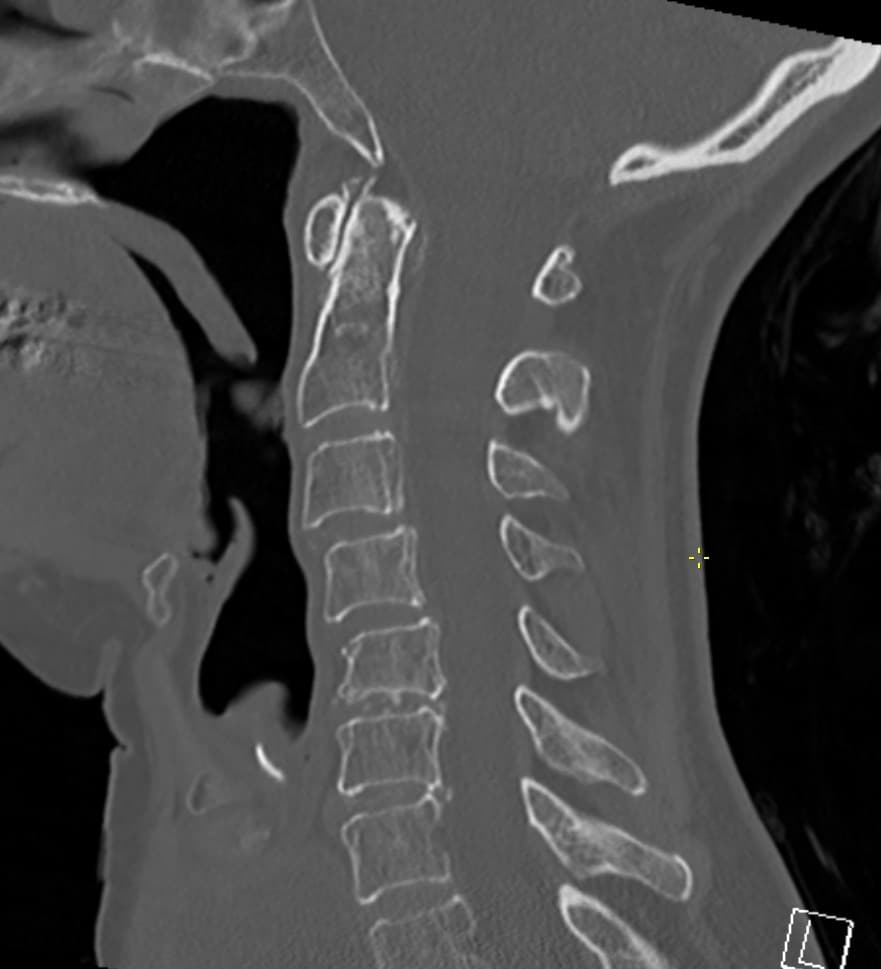

Hvordan en fokuseret second opinion kan forbedre frakturkarakteristik og støtte mere sikker planlægning.

Læs artikel